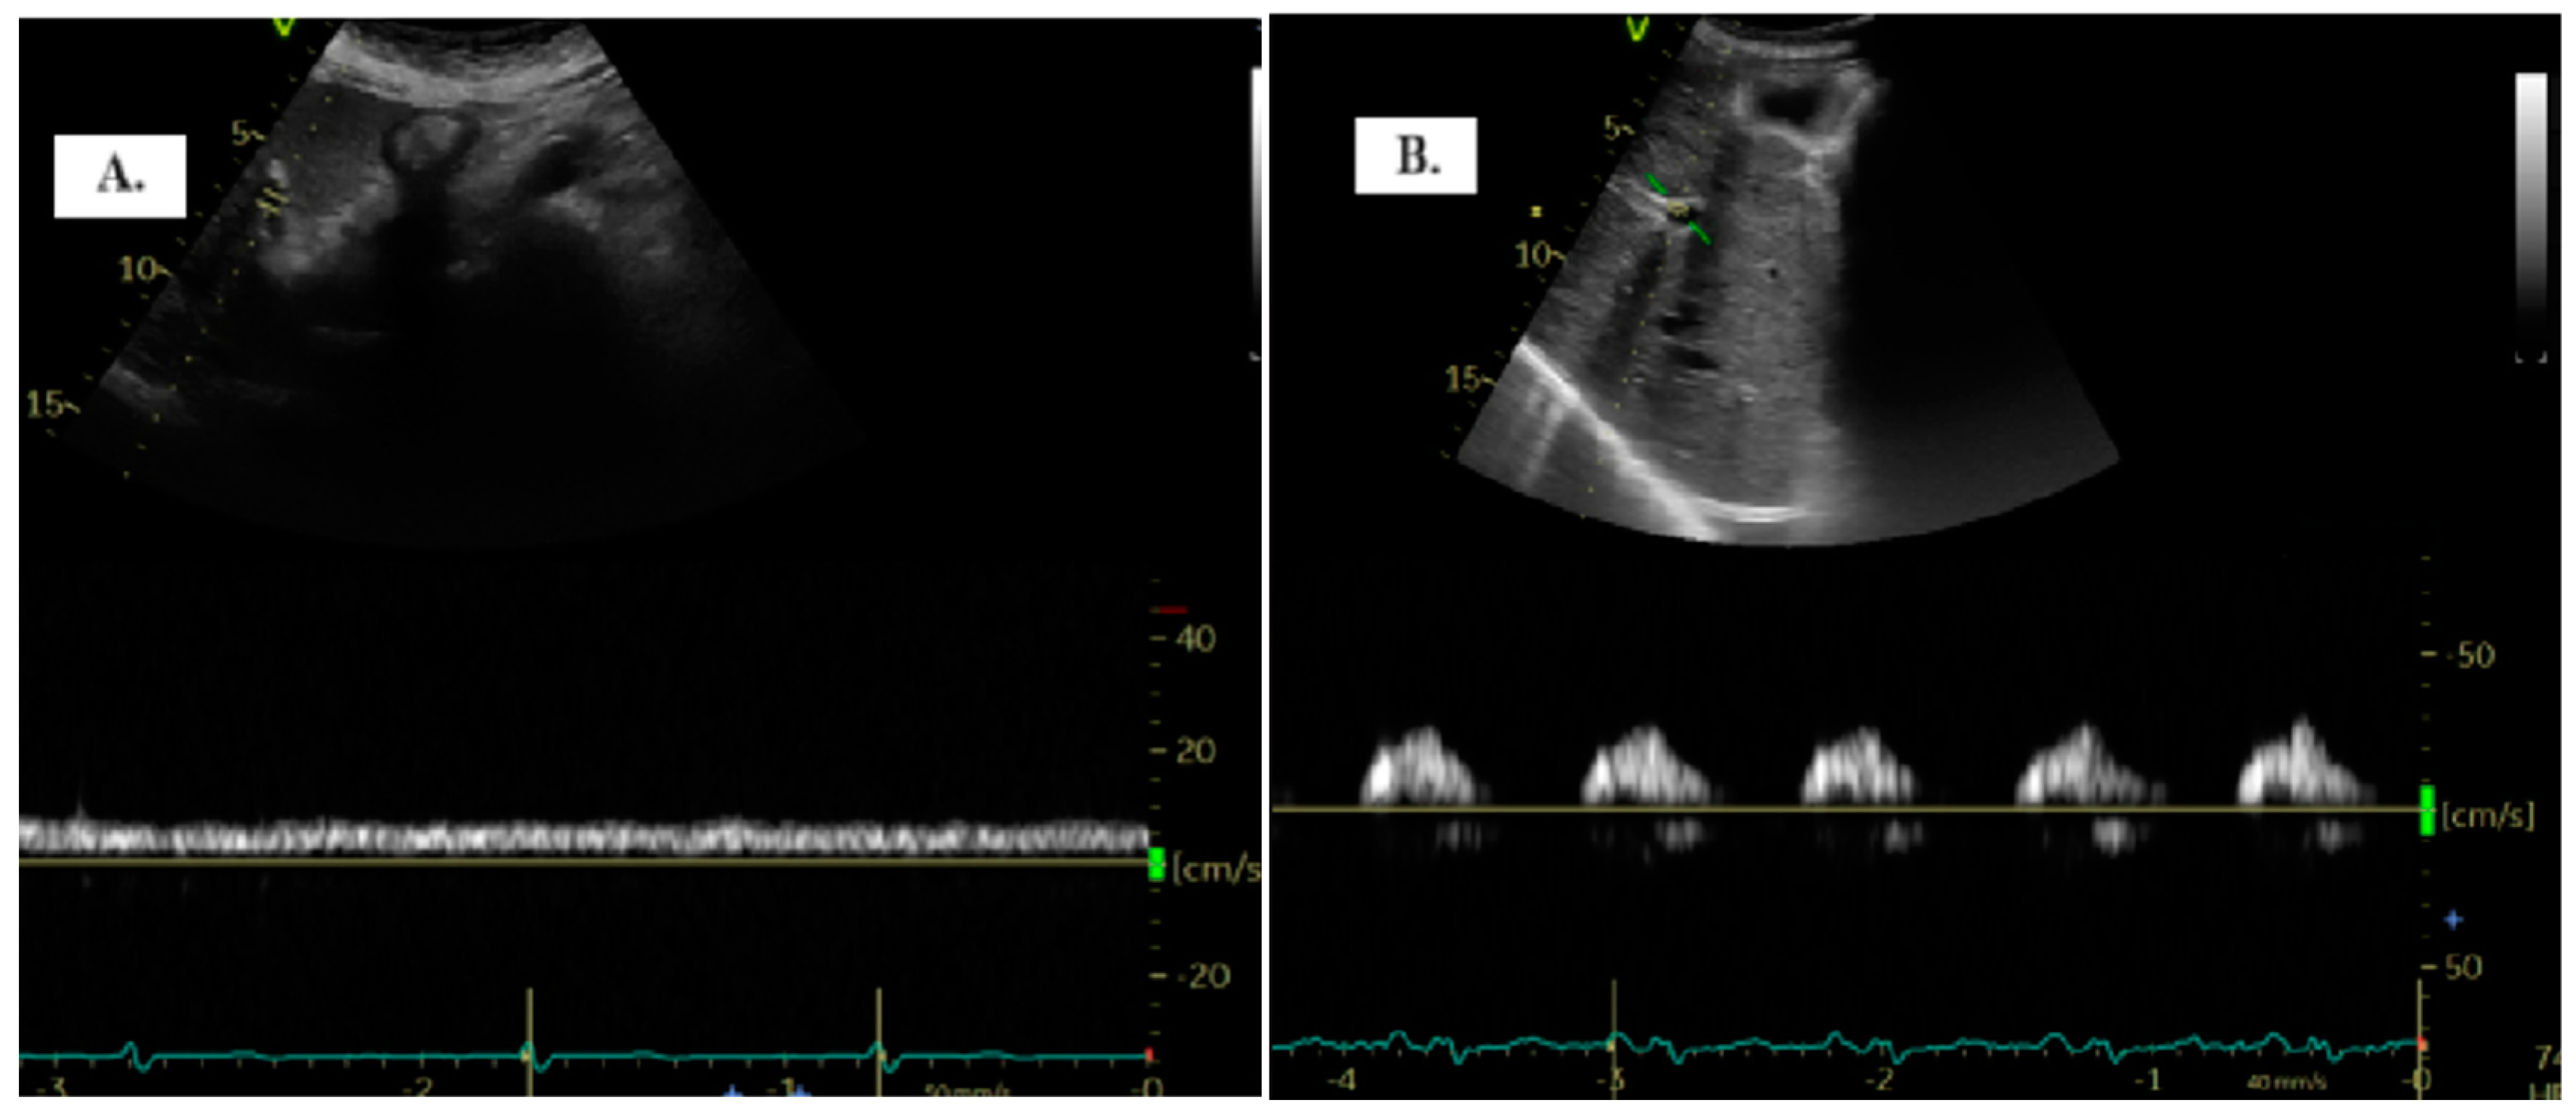

To detect the portal vein (PV), patients were positioned in the dorsal decubitus position in post-expiratory apnea. Either the sub-xiphoid or lateral transhepatic windows can be used for imaging. The PV assessment is conducted using color Doppler and Pulsed-Wave Doppler with a baseline velocity of 20 cm/s, synchronized with the electrocardiogram. Maximum (Vmax) and minimum (Vmin) velocities were measured, and the portal vein pulsatility index (PVPI) was calculated using the formula: maximum velocity − minimum velocity/maximum velocity) × 100 (Figure 1). In some cases, tilting the transducer slightly upward from the mid-axillary transhepatic window helped in visualizing the PV more clearly [9].

Figure 1.

The two distinct types of portal vein Doppler patterns: continuous (A) and discontinuous (B).

The quantification of portal vein pulsatility can be achieved through the PVPI. In normal conditions, PVPI <30% and pathologically >50% [11].